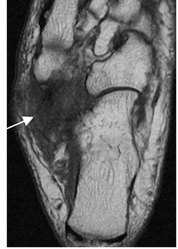

Fig 119 B. Sindrome del seno del tarso.

RM axial en T1. Cambios inflamatorios crónicos post- trauma, que reemplazan la grasa normal del espacio.